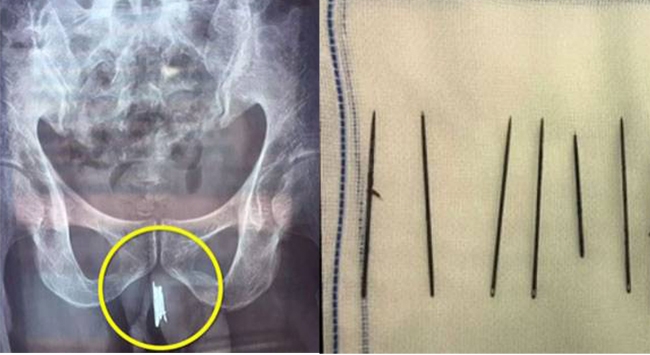

കടുത്ത വേദനയുമായി ഷെന്യാങിലെ ആശുപത്രിയില് എത്തിയ യുവാവിന്റെ ജനനേന്ദ്രിയത്തിലൂടെ പുറത്തെടുത്തത് 15 സൂചികള്. വേദന സഹിക്കാന് സാധിക്കാതെ വന്നതോടെയാണ് ഇയാള് വൈദ്യ സഹായം തേടിയത്. തുടര്ന്ന് നടത്തിയ ശസ്ത്രക്രിയയിലാണ് 15 സൂചികള് നീക്കം ചെയ്തത്.

യുവാവിനെ ആശുപത്രിയില് എത്തിച്ചത് സുഹൃത്തുക്കളും ബന്ധുക്കളും ചേര്ന്നാണ്. യുവാവ് ജനനേന്ദ്രിയത്തില് സൂചികള് കുത്തിയിറക്കുന്ന കാര്യം അവര് അറിഞ്ഞിരുന്നില്ല. ശസ്ത്രക്രിയയ്ക്ക് ശേഷം പുറത്തെടുത്ത സൂചികള് ബന്ധുക്കളെയും സുഹൃത്തുക്കളെയും കാട്ടിയപ്പോഴാണ് വേദനയുടെ കാരണം അവരും മനസ്സിലാക്കിയത്.

യുവാവിന് മാനസിക വിഭ്രാന്തിയുള്ളതായി ബന്ധുക്കള് വ്യക്തമാക്കി. യുവാവ് സ്വയം ജനനേന്ദ്രിയത്തില് കഴിഞ്ഞ കുറേ വര്ഷങ്ങളായി സൂചികള് കുത്തി കയറ്റുകയായിരുന്നുവെന്നും ബന്ധുക്കള് പറയുന്നു.